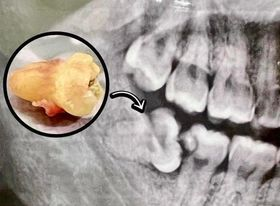

Surgery

Dental surgery is any of a number of medical procedures that involve artificially modifying dentition; in other words, surgery of the teeth (wisdom tooth), gums and jaw bones.